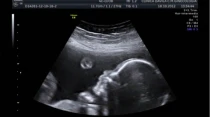

Embriu00f3n de 7 a 8 semanas / Cru00e9dito: Steven O'Connor, M.D., Houston Texas

Estudio muestra que antes de nacer ya hay diferencias entre el cerebro masculino y femenino

Apr 3, 2019

Un nuevo estudio científico encontró diferencias significativas en las formas en que los cerebros masculinos y femeninos funcionan en el... Leer más